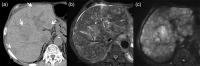

MRI is widely used in clinical practice for detecting liver diseases. Since the introduction of gadoxetic acid, MRI has become the most effective modality for the detection and characterization of focal liver lesions. According to previous meta-analyses, the area under the receiver operating characteristic curve (AUROC) was 0.97-0.99 for the diagnosis of small hepatocellular carcinoma (≥ 2 cm) by gadoxetic-acid-enhanced MRI. Moreover, the AUROC for the diagnosis of colorectal liver metastases was significantly high (0.98). Despite gadoxetic acid's drawbacks, its clinical utility outweighs them, making it the contrast agent of choice in routine liver MRIs. Moreover, clinically, liver MRI has become more prevalent for a quantitative assessment. Liver fibrosis can be evaluated using MR elastography; whereas, hepatic steatosis and iron overload can be evaluated using proton density fat fraction, with high accuracy and reproducibility. This article reviewed the usefulness of liver MRI, which can be a comprehensive imaging modality in clinical practice.